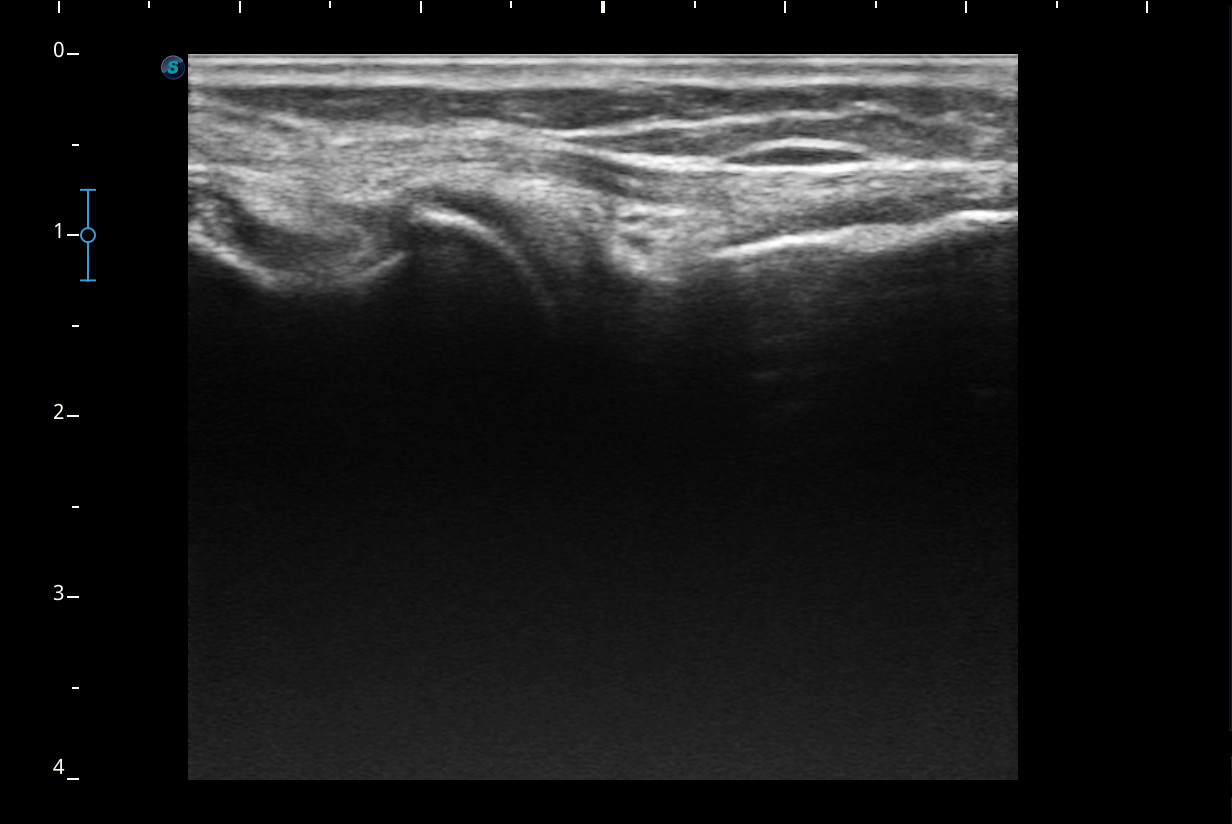

Se realiza ecografía de rodilla.

Descripción de los hallazgos ecográficos y las imágenes más relevantes para la resolución del caso

Rodilla sin derrame articular. No se aprecian lesiones en Ligamentos colaterales. Ligamento rotuliano sin hallazgos valorables. Rotura menisco interno y dudosa fisura menisco externo. Tendones rotuliano y cuadricipital normales.